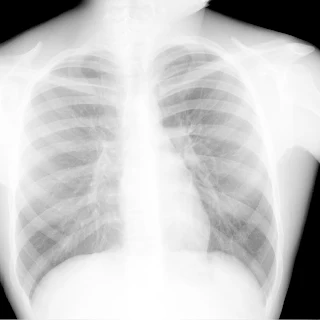

Флюорограма №74

Легені без вогнищево - інфільтративних змін. Корені не змінені. Синуси вільні. Серце норма.